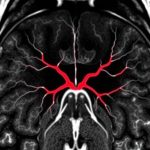

- В тот момент, когда человек отказывается от наркотиков, то он сталкивается с ощущением дискомфорта, в дальнейшем, оно начинает переходить в сильные страдания. Естественно, происходит угнетение центральной нервной системы, так как будут включены защитные функции со стороны организма. Сюда можно отнести возникновение таких симптомов, как тошнота, рвота, тахикардия, бессонница, и т.д.

- Не стоит забывать, что детоксикация — это и есть, процедура, когда через капельницу больному вводятся специальные медикаменты, они станут разрушать наркотические вещества, существенным образом ускоряя их выведение из организма. Таким образом, родственники больного должны осознавать и понимать, как правило, капельница будет включать витамины, минералы. Это и те самые препараты, предназначенные для укрепления иммунитета.